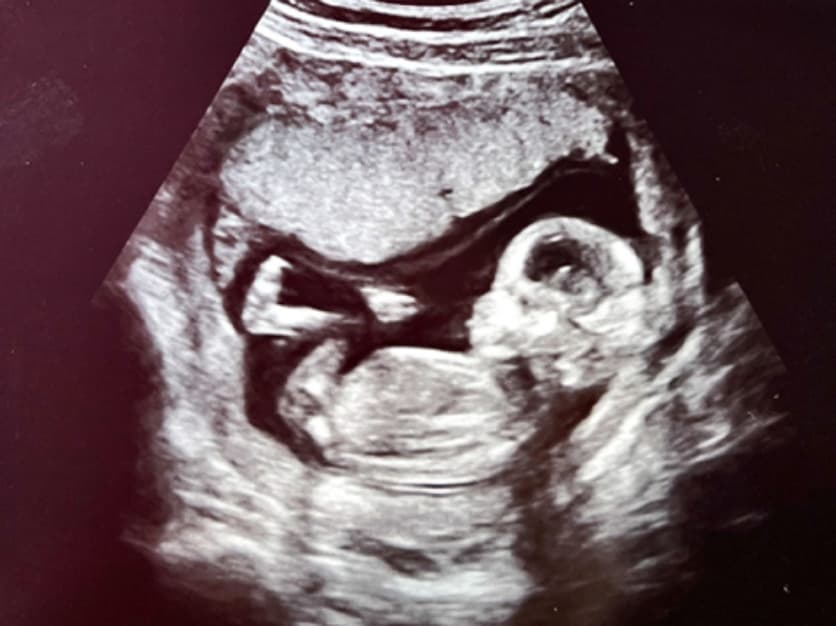

胎児エコー写真

4D胎児エコー写真

• 妊婦健診の中でいつでもご希望の時に、お腹の中の赤ちゃんの状態を立体的に、そして動きまでリアルにご覧いただける超音波技術を用いた4Dエコー外来が受診できます。

• お腹の中のお子さまの様子を鮮明にご覧いただくことが可能です。(希望者のみ:2,160円/回)

(6週)

(10週)

(12週)

(30週)

(36週)